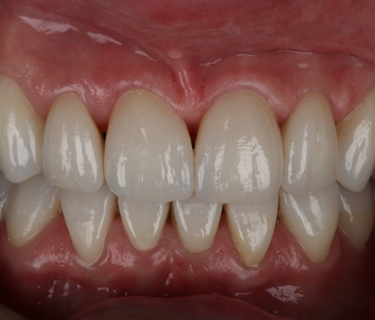

On the day of cementation, the temporary milled restorations were once again removed, and the exquisite gingival health observed (Fig. 18). By using the milled Telio-CAD temporaries the patient has far better control over their oral health around the restorations and the gingival health is always far superior to that when using a conventional ‘shrink-wrap’ technique. The new restorations were tried onto the teeth and the fit and aesthetics assessed. Figure 19 shows the exact replication of shape and size between the temporary (bottom) and final (top) restorations at this try-in stage. The teeth were prepared for bonding following standard protocol of air-abrasion to remove any biofilm and to create enhanced micromechanical retention, followed by a 2% chlorhexidine scrub.

The patient returned after two weeks, and the final restorations were once again assessed. All margins, occlusion and excursions were re-checked and there were no further adjustments necessary (Fig. 24 & 25). Note the beautiful tooth morphology and the detailed surface texture that is achievable with modern digitally designed tooth libraries and state-of-the-art milling machines. The transfer of digital design to final restoration is an exact replication and this can be seen on the comparison of digital overlay against the final zirconia restorations in Figure 26

By approaching multiple restorations in the same methodical and planned approach every time, the SmileFast protocol, integrated with a digital ceramic workflow, guarantees predictable and consistently excellent aesthetic results. Figure 6 and 26 show the restored upper arch with composite (Fig. 6) and ceramics (Fig. 26) in direct comparison to the planned digital design; the accuracy of transfer is very precise, with the natural texture and the detailed morphology being replicated exactly.

Traditionally, zirconia restorations have lacked life-like character and have appeared too opaque or absent of the subtle details of natural teeth. Using the new ZirCAD Prime Esthetic, which is a combination of 4y-tzp and 5y-tzp zirconia, with the revolutionary integrated gradient technology, this material remains highly aesthetic yet retains the strength and functional properties that are synonymous with zirconia restorations. With the subtle external staining applied by a skilled ceramist, the final aesthetics are incredibly life-like with light absorption and reflective properties much closer to natural teeth than any other restorative materials in it’s class (Fig. 27).